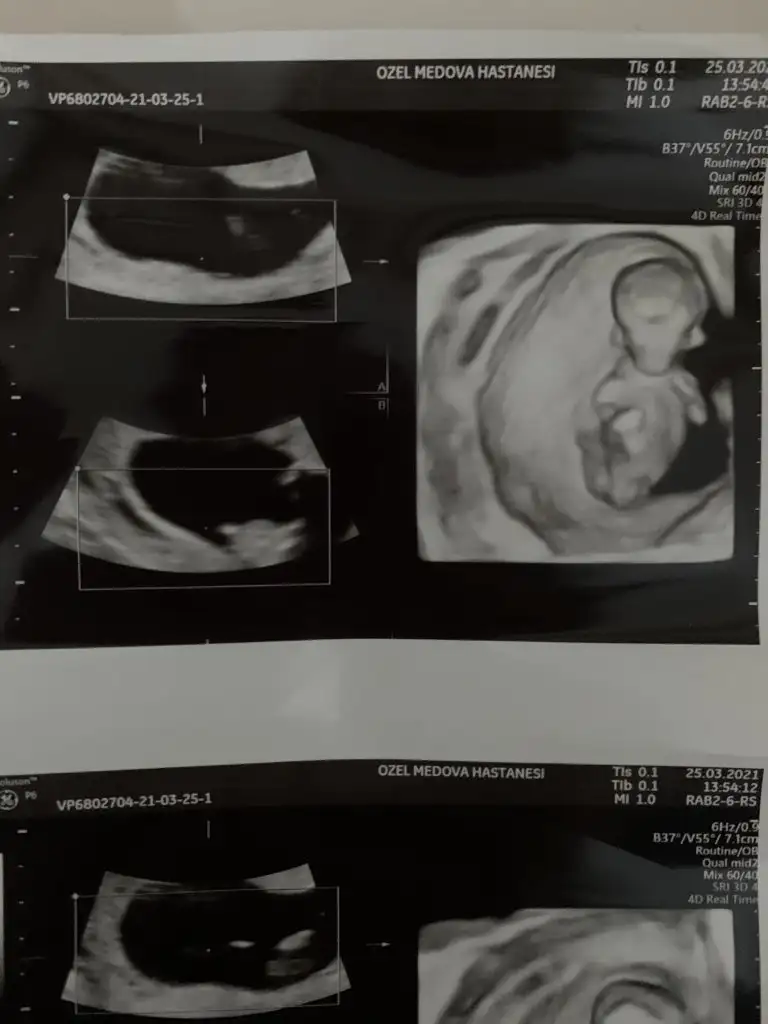

dr soylemeden siz gorun genital nub teorisi ( bebegin cinsiyeti)

Erkek ve kız için 11 + 12+ yada 13 hafta usg görüntüsü olmalı açıklamalar asagıda yazıyor 😊 rabbim herkesin gönlüne göre nasip etsin inşallah .. ecmain

[/B]Eki Görüntüle 473828 gordugunuz gibi ust taraftaki simgedende anlasildigi gibi eger cikinti paralel ise kiz

yok 30°lik bir aciyla yukari dogru bakiyorsa %99 oglunuz olacak demektir simdi bi kac ornek resimler daha koyacagim kiziminkide dahil

Eki Görüntüle 473831 simdi burada cikintilara bakin eger bel popo cizgisine paralel ise kiz

yok 30 derecelik bir aciyla yukari bakiyorsa erkek

iste o nub teorisi kizlar dr buradan yola cikiyor